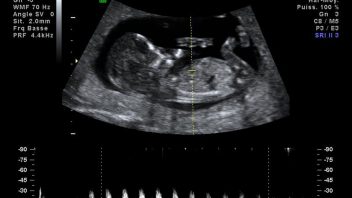

Nejčastější potíže v těhotenství